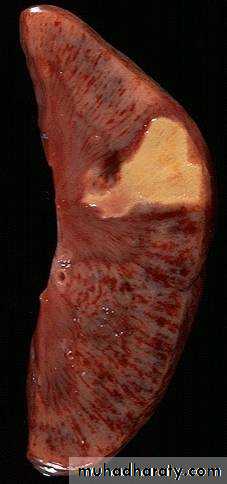

(Infarctions of the spleen (wedge –shaped pale areas caused by obstruction of spleenic artery

Coagulative necrosis (infarction) of kidney